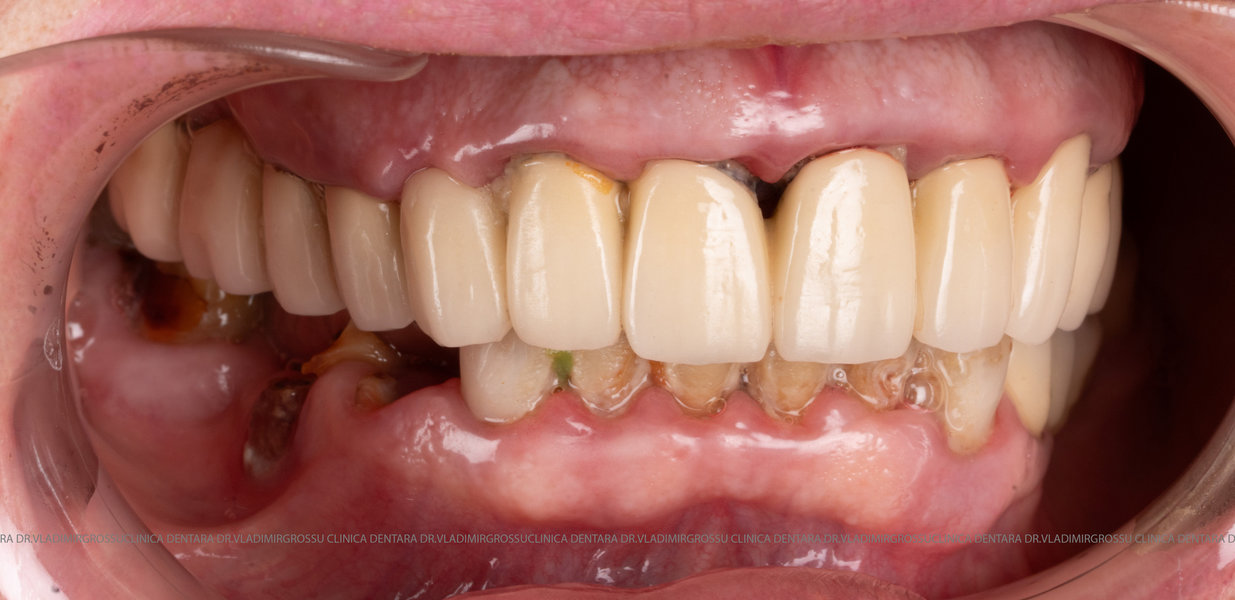

Această metodă este indicată pacienților cu edentație totală sau cu lipsuri dentare multiple, când dinții rămași nu mai pot susține o proteză fixă eficientă. Procedura se desfășoară în două etape:

- Prima etapă constă în inserarea implanturilor și fixarea unei proteze provizorii, realizate de obicei din masă plastică frezată, ce este montată în a doua sau a treia zi postoperator. Suturile sunt îndepărtate după 5-7 zile.

Caz 1